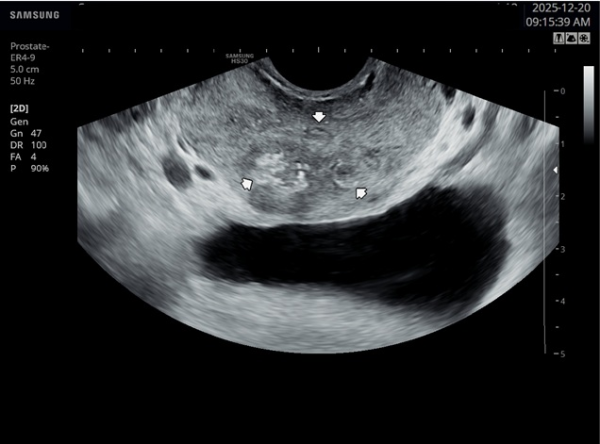

내원 첫 당일 경직장 전립선 초음파 검사상 사정관 입구의 결석들과 사정관 낭종이 관찰되는 사진입니다.(NIH:24)

On the initial transrectal prostate ultrasound, the image shows the presence of calcifications (stones) at the opening of the ejaculatory duct as well as a cystic lesion within the ejaculatory duct (ejaculatory duct cyst).(NIH:24)

주 2회 14주 동안 전립선과 정낭, 사정관과 정관등의 표적 치료후 사정관의 낭종등이 치료 되고 있는 경직장 전립선 초음파 검사 자료 입니다.(NIH:13)

This transrectal prostate ultrasound image shows improvement of an ejaculatory duct cyst after targeted treatment of the prostate, seminal vesicles, ejaculatory ducts, and vas deferens.

The treatment was performed twice a week over a period of 14 weeks. As a result, the previously noted cyst in the ejaculatory duct is gradually resolving, indicating improved drainage and recovery of normal ductal circulation.(NIH:13)

For the patient, this means that small stones and a cyst are blocking the natural passage where semen normally flows. These findings can explain symptoms such as pelvic pain, difficulty with ejaculation, blood in semen, or infertility.

Treatment may involve addressing these blockages to restore normal flow and relieve associated symptoms.

내원 당일 경직정 전립선 정면 사진상 전립선내의 이행구역과 중심 구역 등에 광법위하게 관찰되는 결석과 우측 전립선 부위의 결석이 더 진행된 사진입니다.(NIH:24)

On the transrectal ultrasound image taken on the day of your visit, we can see that multiple stones are widely distributed within the transition zone and central zone of the prostate.

In addition, the image shows that the stones on the right side of the prostate are more advanced and progressed compared with other areas.(NIH:24)

주 2회 14주 동안 전립선과 사정관, 정낭 그리고 정관등의 표적 치료후 전립선의 결석이 치료되고 있는 경직장 전립선 초음파 사진입니다.(NIH:13)

This transrectal prostate ultrasound image shows improvement of prostatic stones after targeted treatment of the prostate, ejaculatory ducts, seminal vesicles, and vas deferens.

The treatment was performed twice a week for 14 weeks, and the previously observed prostatic calcifications are gradually resolving, suggesting improved drainage and recovery of prostate function.(NIH:13)